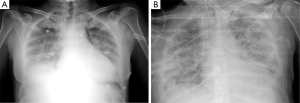

During the acute phase, within 48 h from onset, CXR could not show any pathological sign, after then a rapid worsening occurs, and diffuse bilateral opacities appear as ‘white lung’ image (Figure 1A); moreover, alveolar bronchograms and atelectasis are a frequent finding. In this phase, lung volumes are dramatically reduced and start posing a serious challenge for mechanical ventilation. For a specific radiologic diagnosis, the CXR should not show sign of heart failure such as heart shape enlargement, septal lines and pleural effusion: a comprehensive clinical evaluation is mandatory to perform an accurate differential diagnosis. In the intermediate or proliferative phase, occurring within 1–2 weeks from ARDS onset, the CXR aspect stabilizes presenting usual asymmetric consolidation and persistent diffuse infiltrates. At this stage, the lung tissue is prone to initiate a fibrotic degeneration process. The late or fibrotic phase is the most variable phase, influenced by intra- and inter-patient factors that can heavily affect the clinical outcome. In a widely variable interval of time, radiologic findings tend to improve, and the complete lung damage resolution depends on the severity of the ARDS, along with the patient’s response, underlying condition and comorbidities. The lung matrix is characterized by fibroblast proliferation as reaction to persistent inflammation, CXR may show a focal or a diffuse reticular pattern that usually corresponds to an increased physiological dead space. ARDS can resolve completely or progress to irreversible fibrosis: CXR will either show a restitutio ad integrum or a typical fibrotic pattern (Figure 1B).